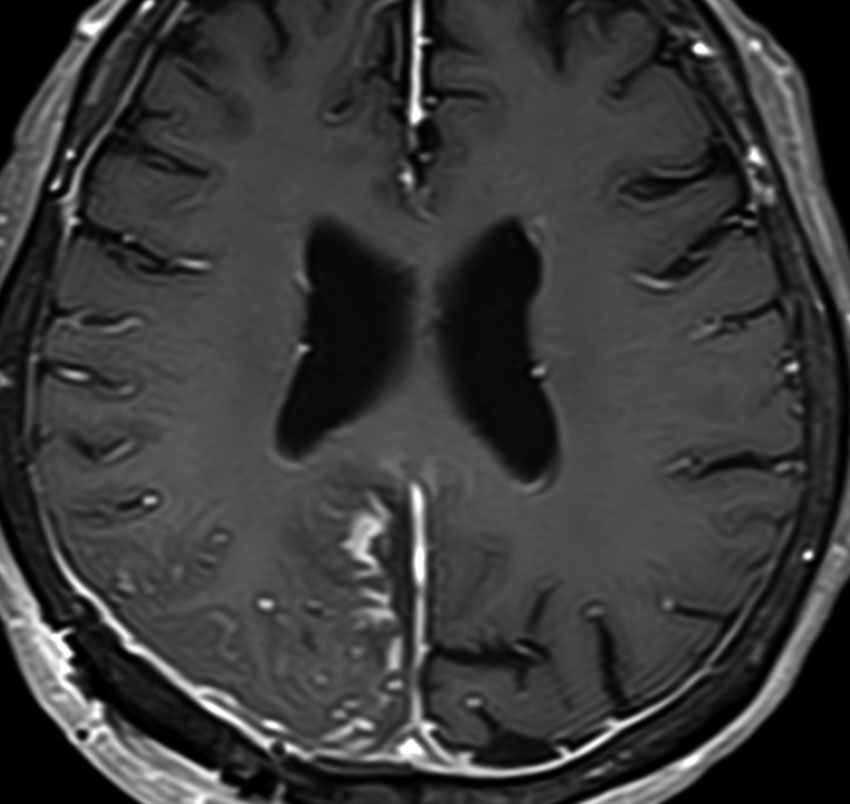

40代男性の大脳鎌テント接合部の硬膜に発生したグレード3です。激しい出血のために腫瘍摘出を部分摘出で中断せざるを得なかった例です。

この例でも,硬膜発生腫瘍ということは手術前の画像診断で解ってはいたのですが,髄膜腫と異なり不整な形をしてのう胞があり,一部は腫瘍壊死でした。